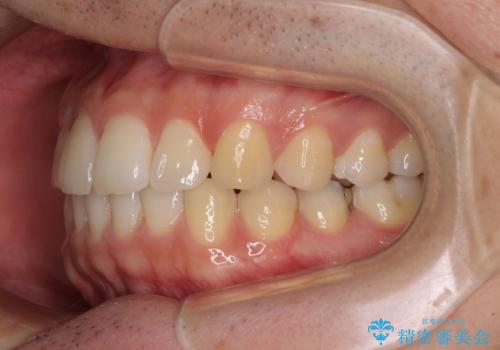

インビザライン・ライトによる矯正治療の後戻り改善

- 矯正治療の後戻りを気にして来院された患者様です。

後戻りは軽微でしたので、インビザライン・ライトにより矯正治療を行うこととしました。

再矯正後の後戻りを防ぐため、歯列排列後に、下顎前歯はワイヤーによる固定を行いました。

下顎前歯の歯列を動かないようにしておくことで、上顎前歯の後戻り防止にも効果を発揮します。